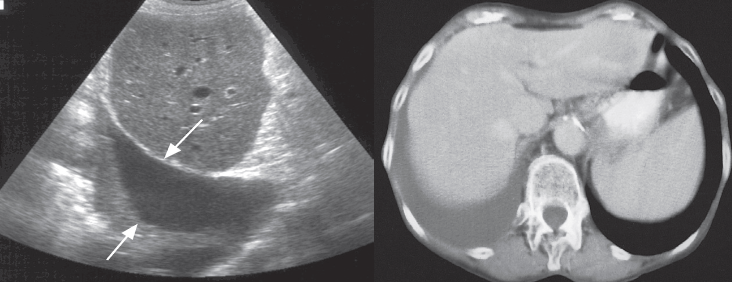

Ultrasound Z

Ultrasound is a simple method of determining whether pleural fluid is present and is a convenient method of imaging control to guide procedures such as pleural fluid aspiration or drainage. Pleural fluid can be recognized as an anechoic area between the chest wall and the lung